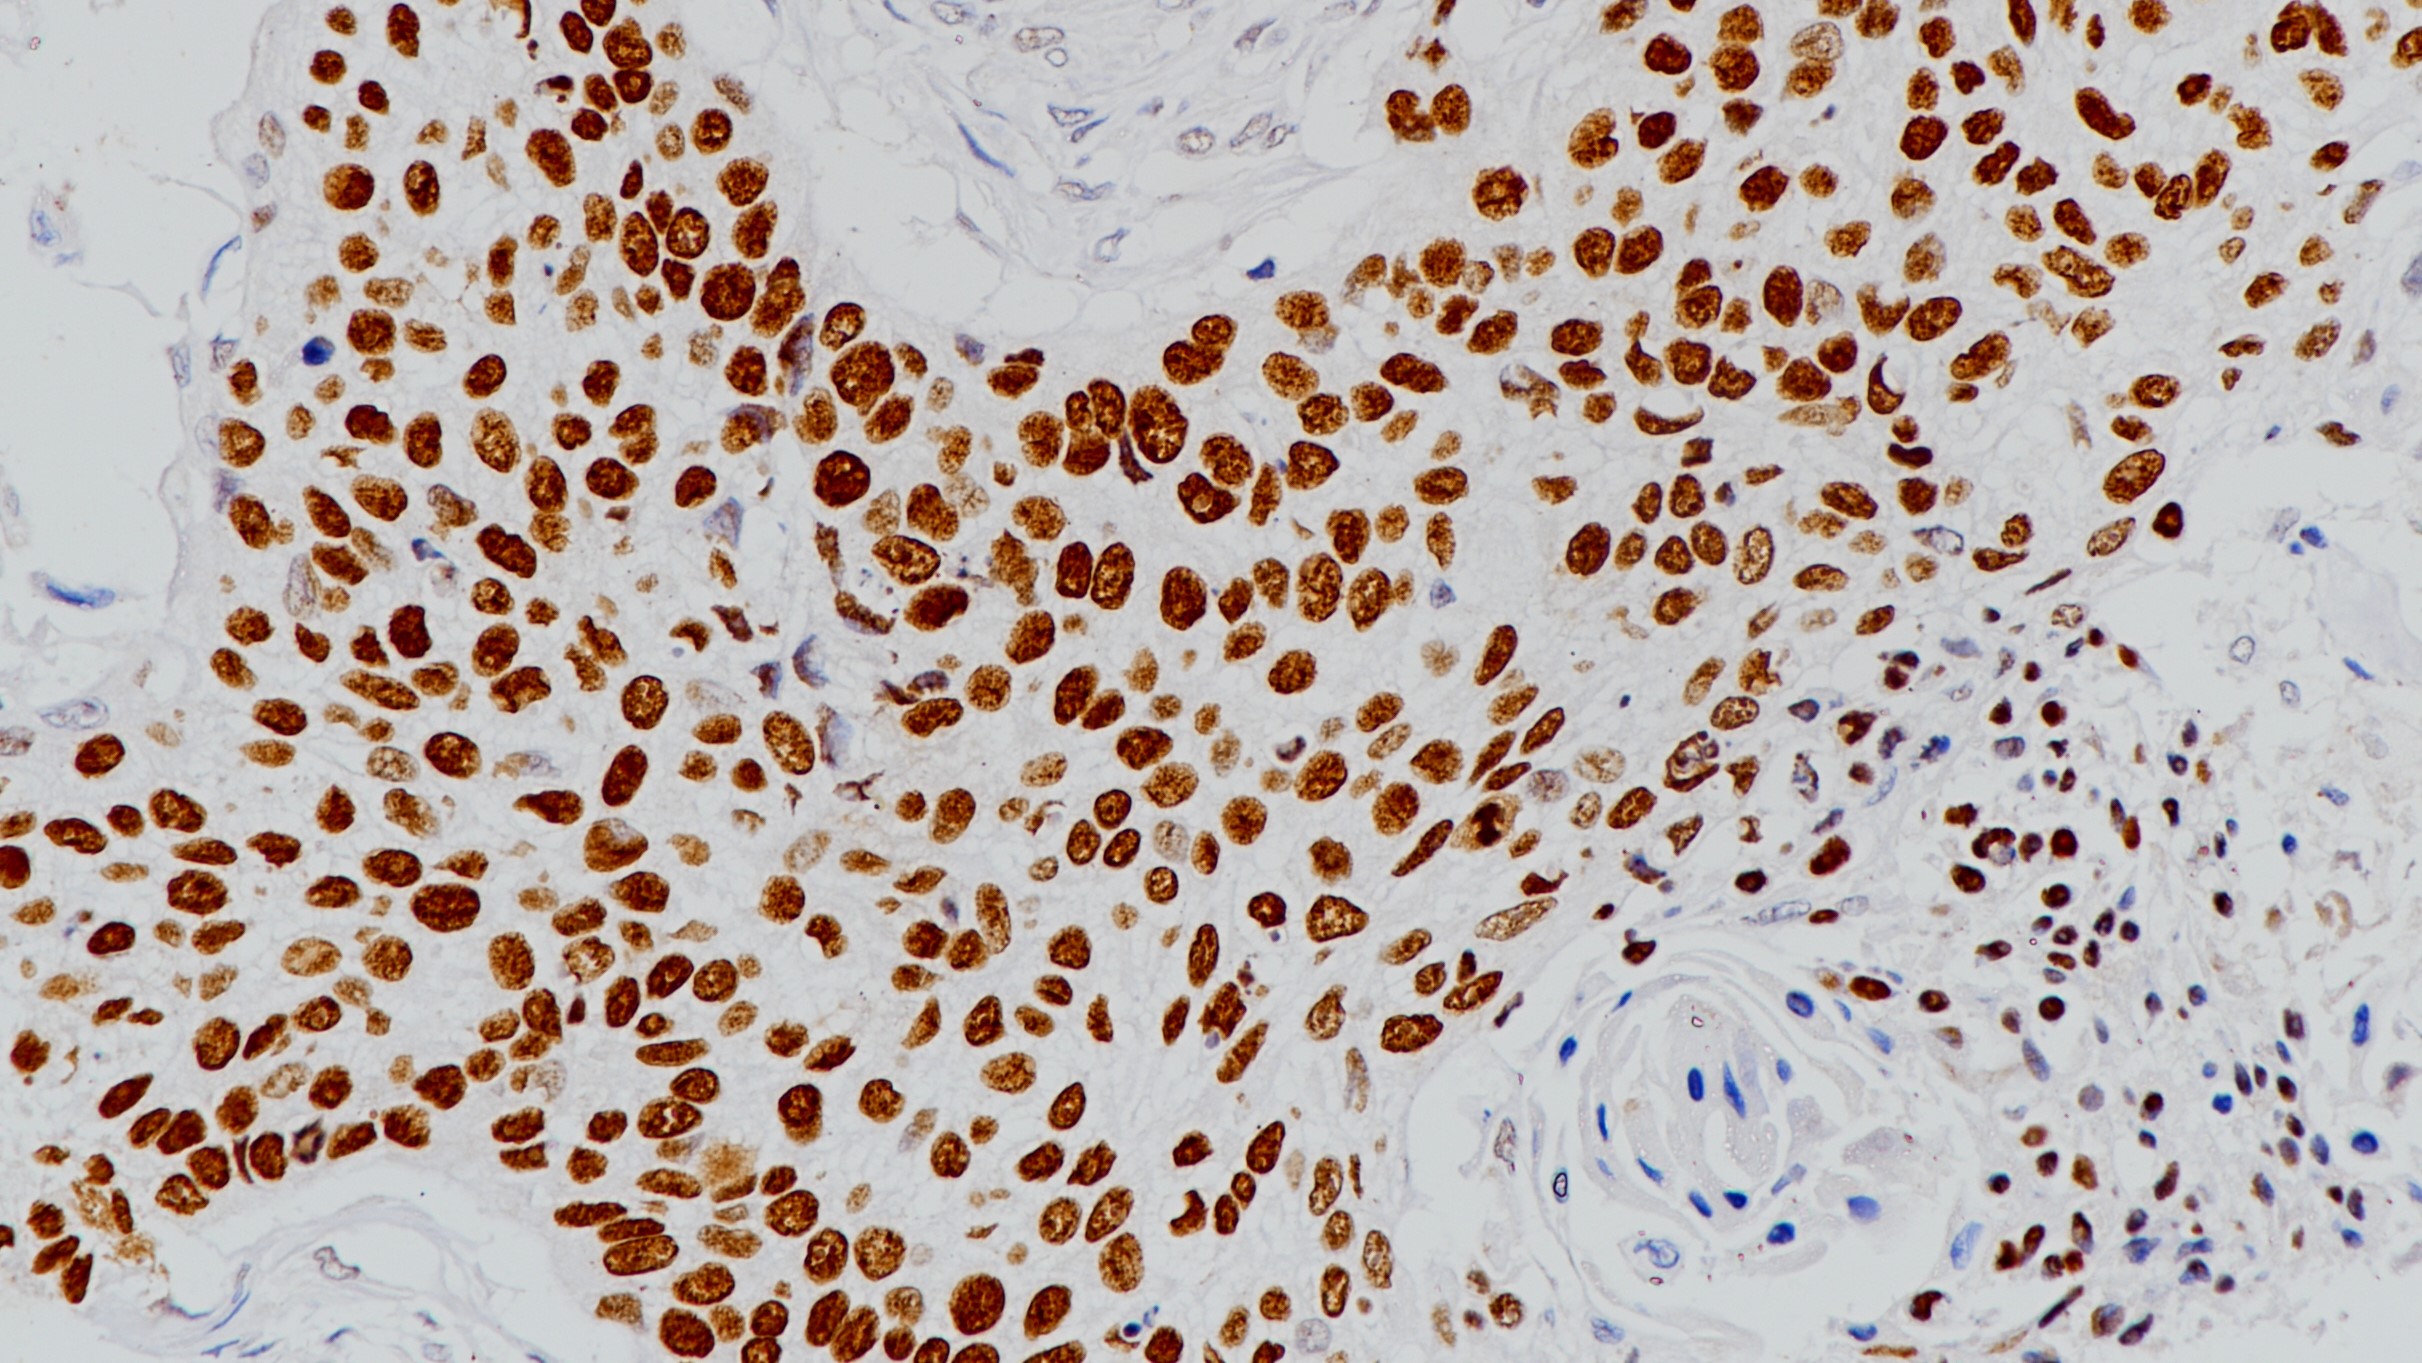

2. Chu PG, Lyda MH, Weiss LM. Cytokeratin 14 expression in epithelial neoplasms: a survey of 435 cases with emphasis on its value in differentiating squamous cell carcinomas from other epithelial tumours. Histopathology. 2001 Jul;39(1):9-16.